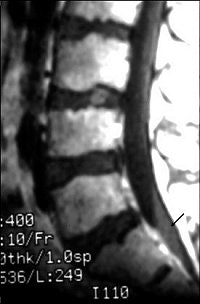

Finally, MRI can be used to study dural tears resulting from spinal fractures. Dural tears may result in entrapment of nerve roots between laminar fragments (images H-J above). Such dural tears may delay, if not preclude, recovery, El-Khoury said. MRI has been found to be 100% sensitive and 74% accurate for diagnosing dural tears as a result of burst fracture, he added.

![]() ![]() ![]() |